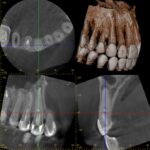

初診時レントゲン・CT

膿が大きく認められました。